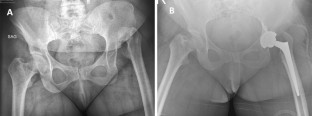

Fig. 2